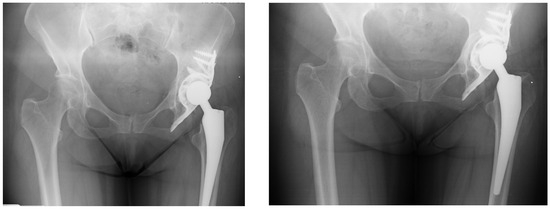

Similarly, there was no significant difference in postoperative VAS scores (p = 0.8), with both groups reporting comparable pain levels one year after surgery (Table 5 and Figure 4).

Figure 4. The images (from 2013—left and from 2015—right) demonstrate the typical phenomenon of bone loss in the least loaded area beneath the dome of the acetabular cage, which is a recognized biological response in such reconstructions.